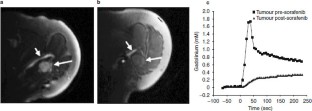

Fig. 2

Fig. 3

Fig. 4